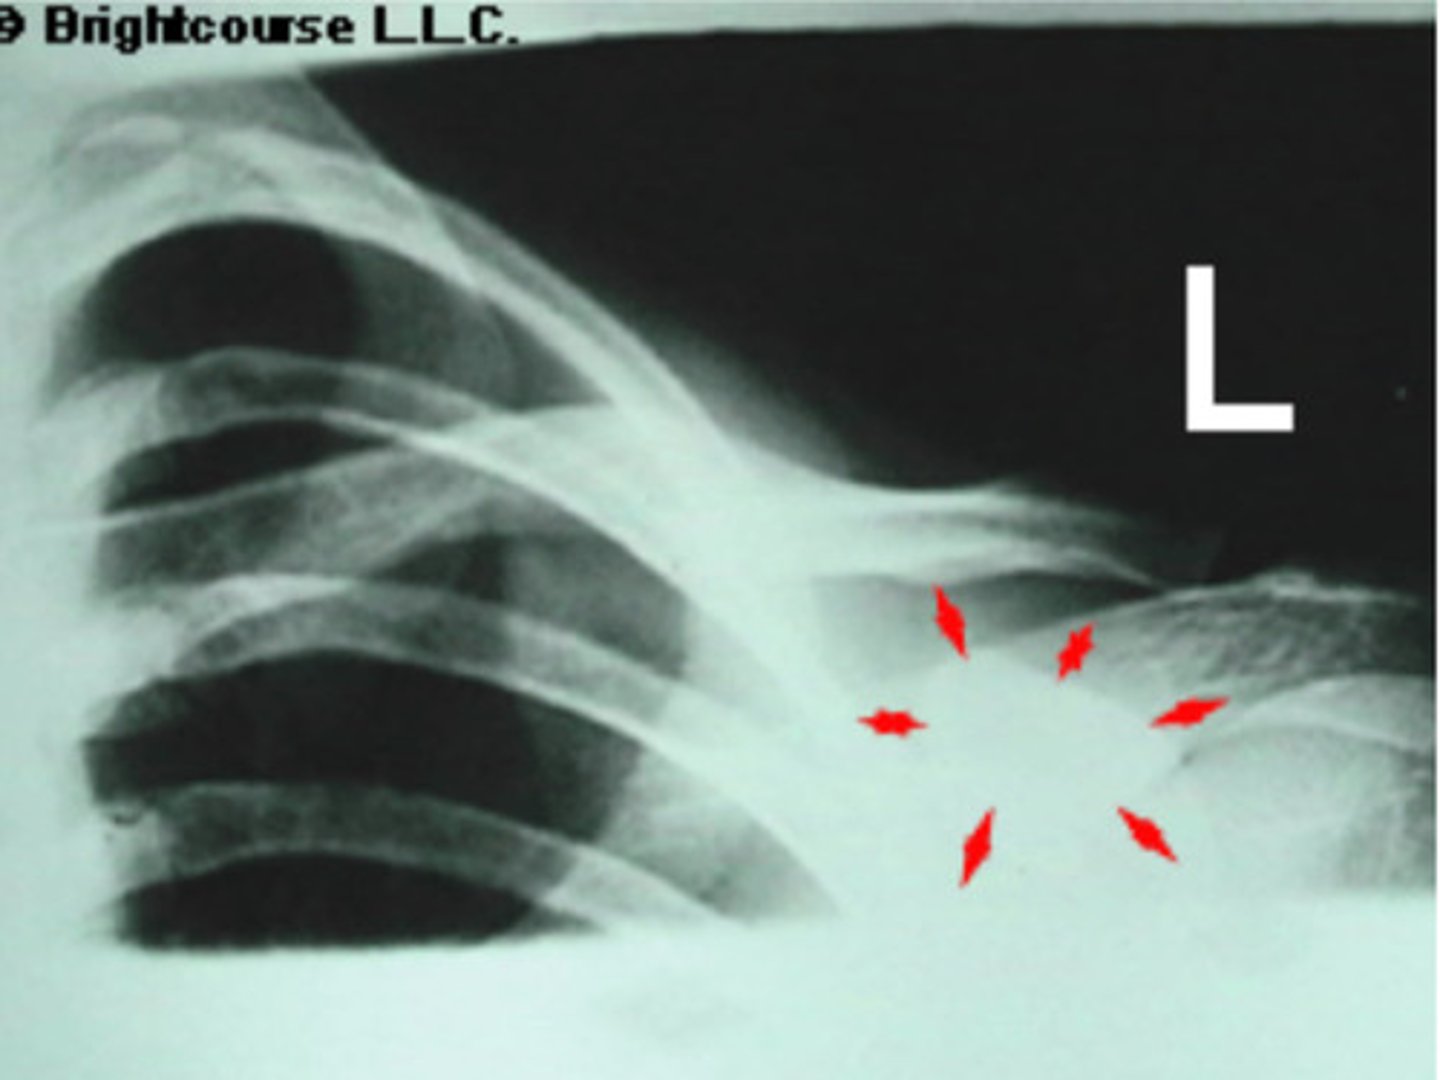

Deltoid tuberosity

What is being pointed out by the arrows in the image?

Lesser tubercle

Proximal shaft of humerus

Mid clavicle